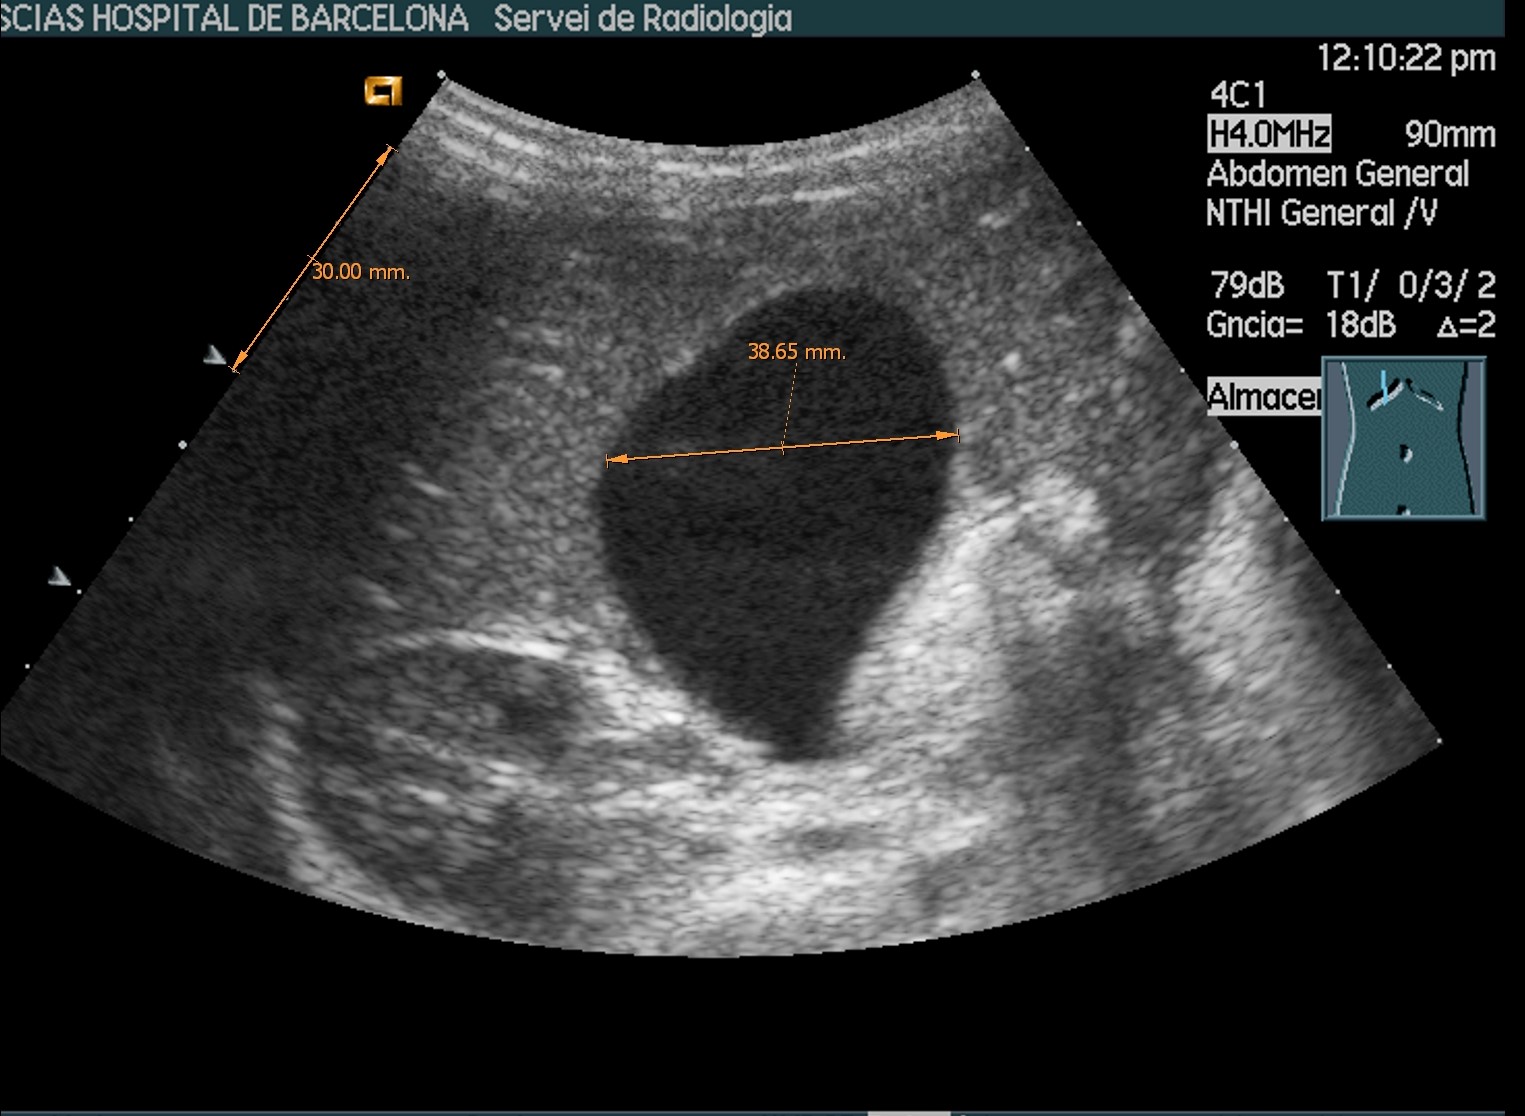

Se realiza ecosonograma abdominal donde se observa una vesícula biliar distendida, de 3,8 cm en el corte transversal, con contenido espeso en su interior, sin dilatación de vías biliares, ni imagen de litiasis.